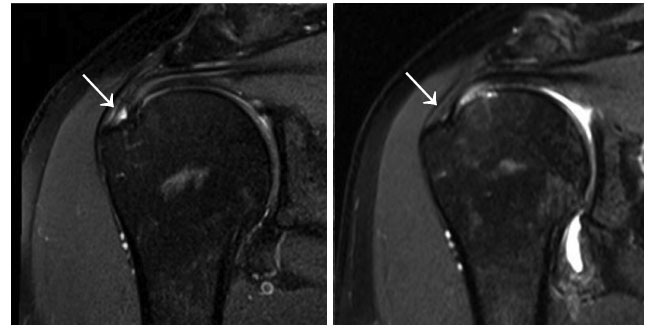

This means that the MRI chances of accurately detecting the possibility of a partial rotator cuff tear are actually there is about 52% Basically the same accuracy odds as a coin Once this 52% is separated into probable and non-probable, then the probable partial rotator cuff tears are confirmed as partial tears with a specificity of2%

Rotator Cuff Tear MRI | New Health Advisor

Figure 1: Rotator Cuff Tear This rotator cuff tear is seen in the The muscle is lit up in bright white and you can see a dark spot indicating the Figure 2: Partial Rupture This is a partial rupture of one of the rotator cuff The red arrow indicates the rupture Figure 3: Complete Rotator Cuff Tear